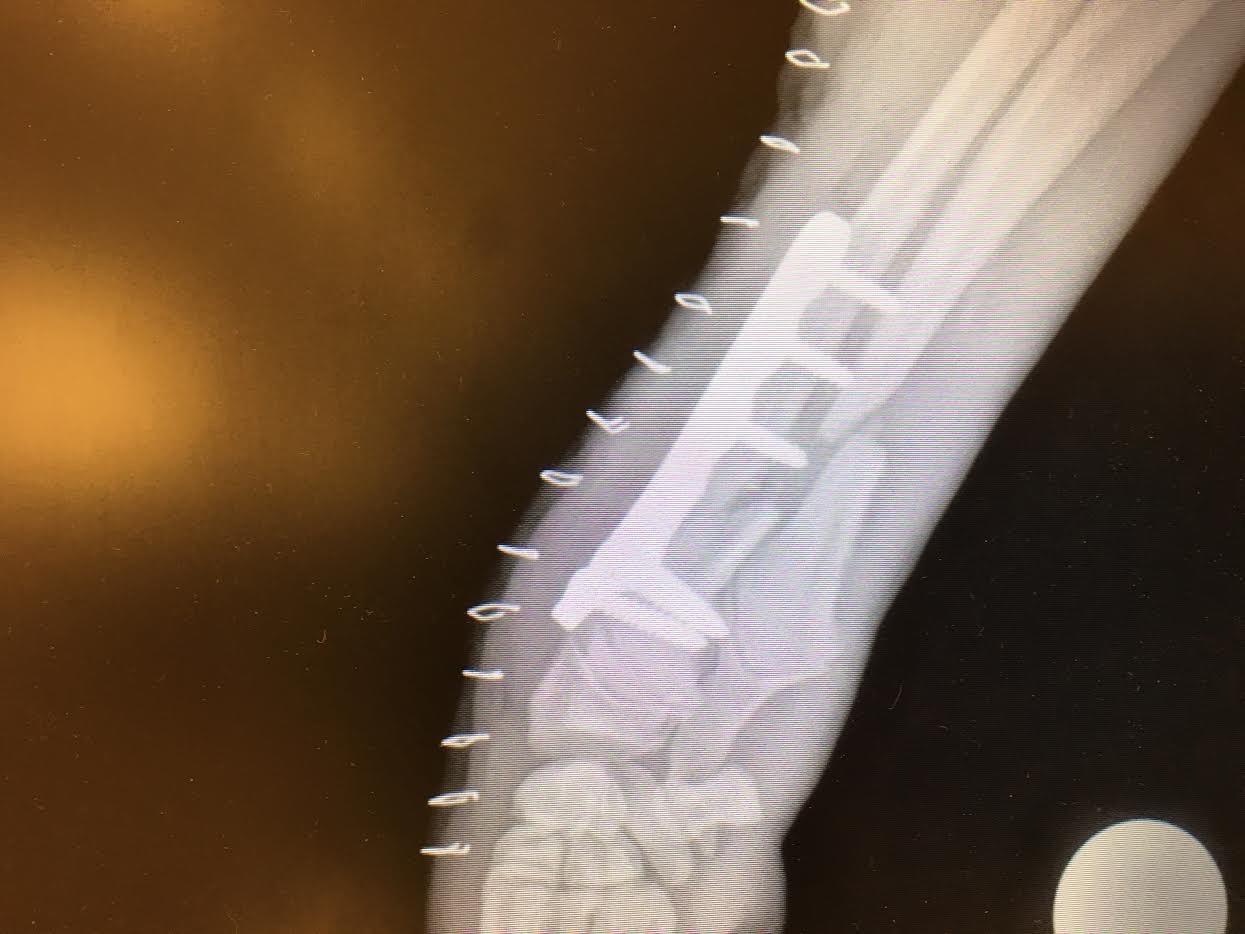

This amazingly sweet pup is one of the best little Angels that does nothing but spread Love and Joy.   She has been fabulous to look after which is a surprise given the major injuries she had to recover from.   Oreo has finally started to walk more normally since we removed the walking brace she had on.   The brace was difficult for her to adapt to because she was missing a rear limb.   We decided it was best to see how well she got around without the brace and she proved we were right.  She began to walk with a more normal gait and also was not as hunched as she had been.   She has to wear the soft bandage for another two weeks and then can have x-rays done to determine if the soft cast can be removed permanently.   We are hoping for her sake it can.